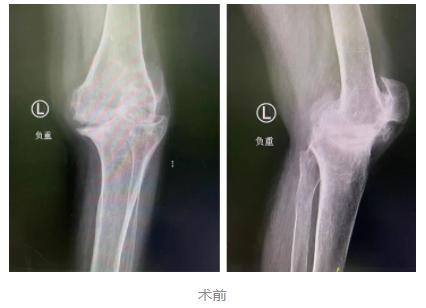

为求进一步治疗,李大姐在家人的陪伴下来到我院关节外科,经过相关系统检查后,确诊为类风湿性关节炎及双膝骨性关节病(KL分级 IV级)。

在结合相关资料及术前讨论后,sararz关节外科张传开、郝亮、王琳、蒋涛手术团队为李大姐在Mako关节置换机器人导航下行左侧人工膝关节置换术。

术前,Mako机器人基于CT进行3D的智能建模,根据患者实际情况个性化定制手术方案。同时,在术中实时根据患者具体软组织张力进行动态调整,辅助手术医生进行精准化、个性化的手术操作。尤其是对截骨、假体安装等重要环节,都进行了全程三维定位,实时将角度、大小、骨质覆盖等重要信息通过数字影像及时传达给手术医生,帮助医生做出准确判断,将手术精度控制在毫米级,完美实现了“精准手术”的要求。